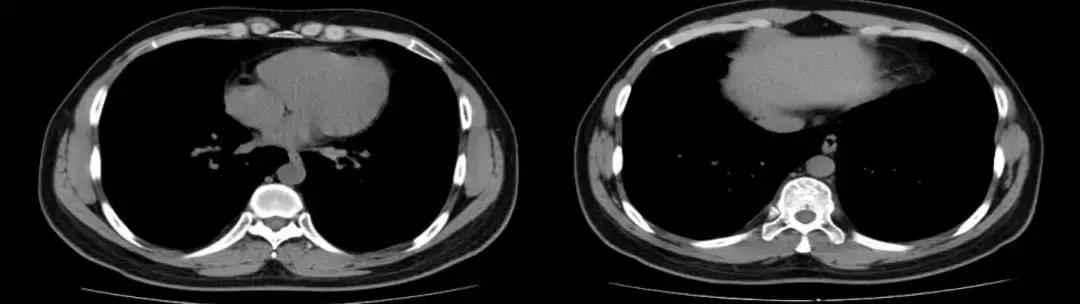

复查胸部CT(2018-07-12):

左肺炎症较前好转,但肺部弥漫性病变较前变化不大。

5、辅助检查:血常规白细胞不高、血红蛋白多次查均为170多g/L;血气分析(多次未吸氧状态):PO2 70多mmHg;血沉最高44mm/h,经治疗后可降至正常;PCT、CRP等感染相关指标均不高;病毒系列、术前四项等均阴性;于我院查自身抗体、ANCA均阴性,抗CCP抗体曾出现阳性,后复查为阴性,就诊于北京协和医院后查ANCA-IgG型 1:10为阳性、抗CCP抗体强阳性、自身抗体阴性;胸部CT提示两肺弥漫磨玻璃病变,左肺肺炎;于北京协和医院行CT引导下经皮肺穿刺术活检病理结果示:肺组织慢性炎,间质纤维组织显著增生,伴较多炎细胞浸润,可见上皮样肉芽肿伴多核巨细胞反应,未见明确坏死,PAS、抗酸、弱抗酸、六胺银染色均阴性,免疫组化CD34(血管+)、Bcl-2(散在+)、SMA(灶+)、CD68(+)、Desmin(-)。经激素治疗3月余后,左肺炎症较前好转,但肺部弥漫性病变较前变化不大。